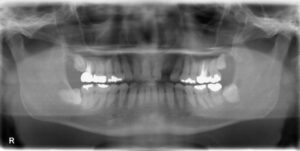

上顎大臼歯2本欠損症例

BEFORE AFTER 50歳女性/上2本欠損/インプラント埋込手術 【治療内容】 左上第一大臼歯、第二大臼歯は他院で…